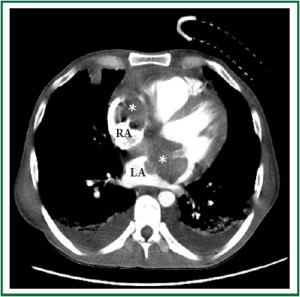

A 46-year-old Caucasian male was admitted to the emergency room with progressive dyspnea, lower limb edema and intermittent fever for 1 month. Past medical history included HIV infection for 20 years, with irregular highly active antiretroviral therapy (HAART) treatment. He had a history of smoking, alcoholism and cocaine addiction. On physical examination, the patient presented with a rapid respiratory rate, blood pressure of 118×68 mmHg and heart rate of 104 bpm. Laboratory data revealed hemoglobin concentration of 6.7 g/dl, white blood cell count of 3.600 /mm3 and platelet count of 22.000 /mm3, with a CD4 count of 49 cels /μl. Computed tomography demonstrated a large, infiltrative, solid mass involving the ascending aorta, pulmonary artery, right ventricle and both atria (Figure 1 and Figure 2) with a lymph node conglomerate in the anterior mediastinum. Transthoracic echocardiography revealed biatrial dilation, mild left ventricular hypokinesia and severe right ventricular impairment. A large echodense mass with irregular borders filled almost completely the left atrium (Figure 3), while another mass was observed inside the right atrium (Figure 4), both attached to the interatrial septum. Increased transvalvular mitral and tricuspid gradients were observed by Doppler study. HAART was started along with intratechal methotrexate, followed by intravenous dexamethasone. Mediastinal biopsy revealed a HHV8-positive PBL. Tumoral cells showed positivity for immunohistochemical markers HHV8, MUM-1, CD138 (focal), CD20 (focal) and Ki67 (high index), whereas CD3 and Epstein-Barr virus (EBV) resulted negative. Bone marrow biopsy showed rare neoplastic cells, compatible with interstitial infiltration by HHV8-positive PBL. Chemotherapy with cyclophosphamide was started. A control echocardiogram after 3 days showed no tumor regression, but significant deterioration of systolic ventricular function. The patient developed hemodynamic instability and worsening of respiratory pattern, requiring ventilatory and hemodynamic support. Despite therapy, the patient died the following day.

Figure 1. Contrast computed tomography of the chest (axial view) showing an infiltrative mass (*) invading the interatrial septum and both atria.